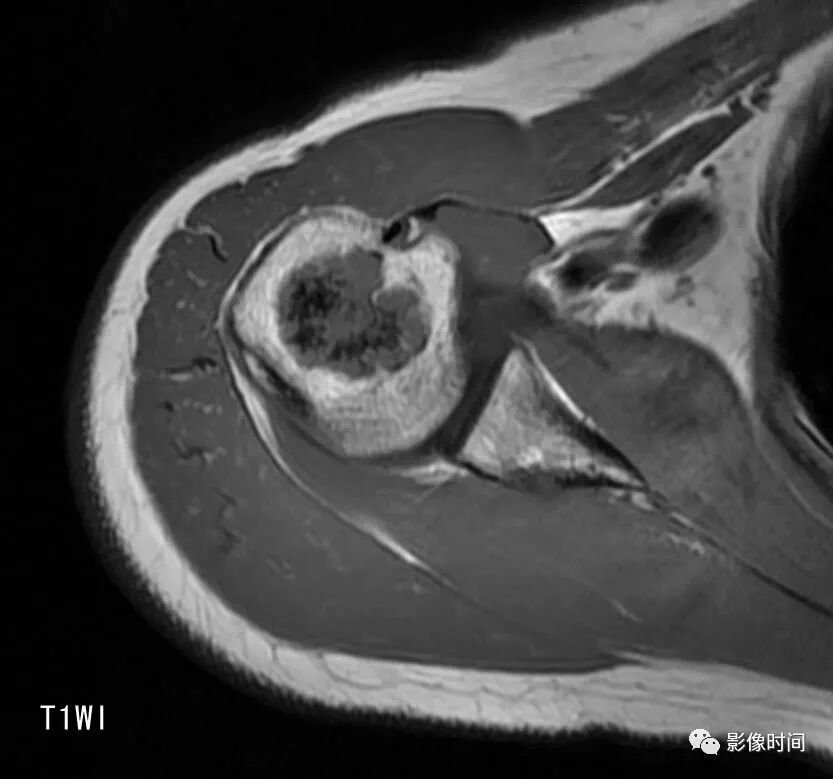

由于瘤软骨多由富含水分及粘多糖的透明软骨构成,故 T1WI 呈偏低信号,T2WI 或 PDWI 呈明显高信号,被低信号的纤维间隔分开呈分叶状(图 24、图 25a-b),增强扫描多呈不均匀分隔状强化(图 25c),主要是纤维间隔强化,瘤软骨强化不明显之故。

图 24  瘤软骨:内生软骨瘤

图 25  瘤软骨:内生软骨瘤